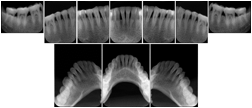

2. A patient requests cosmetic surgery to enhance their facial appearance. The case requires consultation between an orthodontist in New York and an oral surgeon in California. The cephalometric series of 2D projections constructed from the volumetric CT data that is used for the discussion is arranged by a Structured Display for transfer between the two practitioners.

Cephalometric Series Structured Display

Figure OO-2. Cephalometric Series Structured Display